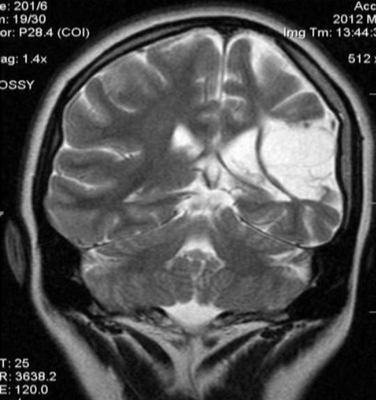

- МРТ головного мозга. В начальной стадии может соответствовать норме. В дальнейшем обнаруживаются атрофические изменения головного мозга, наиболее выраженные в мозжечке и подкорковых ганглиях. МРТ позволяет исключить рассеянный склероз, энцефалит, опухолевые процессы.

Атрофия головного мозга на МРТ

Магнитно-резонансная томография признана одним из наиболее информативных нейровизуализационных методов исследования. В ходе процедуры получают детальные послойные снимки головного мозга, позволяющие оценить соответствие органа нормам.

МРТ актуальна при диагностике посттравматических состояний, воспалительных, опухолевых, нейродегенеративных изменений. Одно из самых тяжелых нарушений, выявляемых с помощью томографии — атрофия головного мозга. Это хроническое прогрессирующее заболевание, сопровождающееся гибелью нейронов, уменьшением объема и плотности структур головного мозга.

Как выглядит атрофия головного мозга на МРТ?

Диффузная атрофия головного мозга с вентрикуломегалией

Явление дифференцируют с истинной гидроцефалией. Главный МРТ-признак атрофии головного мозга — пропорциональное расширение внутренних и наружных ликворных церебральных пространств, что указывает на уменьшение объема структур органа. Выраженность изменений оценивают с помощью церебро-вентрикулярного индекса (ЦВИ Эванса). Учитывают и другие отклонения в ткани головного мозга.

Симптомы патологии на МРТ-снимках:

увеличение ЦВИ Эванса;

расширение субарахноидальных борозд и щелей;

снижение плотности мозговой ткани;

дистрофия белого вещества;

уменьшение долей мозга в размерах.

В зависимости от локализации патологических изменений и степени вовлеченности структур атрофия может быть:

кортикальной (главный признак — инволюция коры на уровне лобных и височных долей);

мультисистемной или диффузной (очаги обнаруживаются сразу на нескольких участках);

генерализованной (изменения происходят во всех отделах органа).